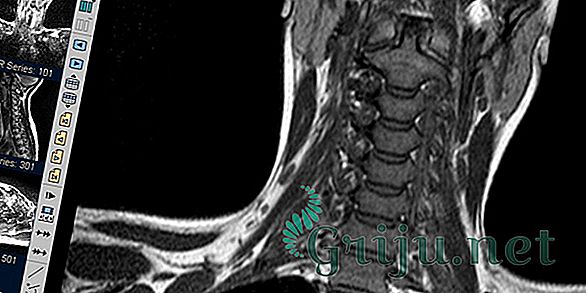

Сначала врач выслушивает жалобы, изучает анамнез болезни и осматривает пациента. Чтобы подтвердить предварительный диагноз и оценить масштабы патологии, больного направляют на инструментальные обследования:

- Спондилографию — рентгенографический метод, показывающий состояние позвонков и степень повреждения суставов;

- Компьютерную и магнитно-резонансную томографию — определяет не только спондилоартроз, но и другие (даже мелкие) патологии шейных позвонков;